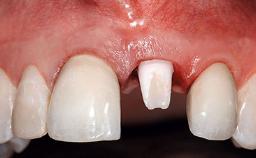

Replacement of a Missing Upper Left Central Incisor, Late Placement of an RC Bone Level Implant and Adjacent Tooth Restoration

A healthy 38-year-old male patient was referred for replacement of a failing tooth-supported cantilever fixed dental prosthesis on teeth 11 and 21. The patient reported a history of trauma at 13 years of age that had resulted in the subsequent loss of tooth 11, as well as endodontic treatment of the adjacent abutment tooth 21. A metal-ceramic cantilever fixed dental prosthesis replacing tooth 11 had been provided by his general dentist several years after the loss of the tooth, with tooth 21 as the sole abutment. At the time of initial presentation, this restoration had been in service for over 20 years.